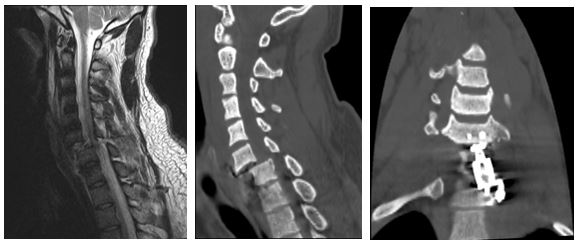

По месту жительства операция была выполнена в ранние сроки после травмы — это принципиально важно при повреждении спинного мозга. Однако полного вправления вывиха позвонков достигнуто не было. В дальнейшем произошло повторное смещение костных структур с сохраняющейся компрессией спинного мозга. Через три месяца после травмы пациент поступил к нам с выраженной болезненной деформацией шейного отдела позвоночника и тяжёлыми неврологическими нарушениями в верхних и нижних конечностях.

С учётом выраженной посттравматической деформации и неврологического дефицита было принято решение о выполнении многоэтапной реконструктивной операции. Команда нейрохирургов и ортопедов (Млявых С. Г., Елисеев А. С., Дедов М. А.) выполнила сложное многоэтапное вмешательство продолжительностью более 10 часов.

• полностью восстановить ось позвоночника;

• устранить патологическое смещение позвонков;

• выполнить адекватную декомпрессию спинного мозга и корешков;

• обеспечить стабильную фиксацию повреждённых сегментов.